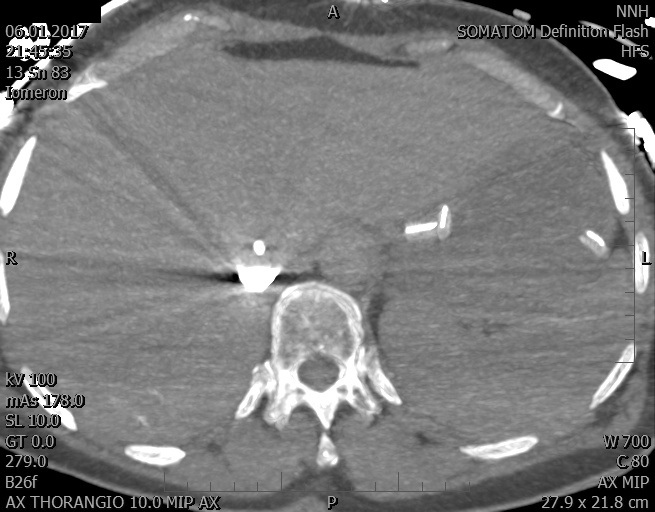

Video 1 - Akutní koronarografie prokázala normální nález na věnčitých tepnách s výjimkou suspekce na lehký spasmus na pravé koronární tepně.Echokardiograficky byla zjištěna těžká dysfunkce dilatované levé komory s nezvětšenou pravou komorou (video 2).

Video 2 - Echokardiograficky byla zjištěna těžká dysfunkce dilatační levé komory s nezvětšenou pravou komorou.Pro nejasnou příčinu zástavy jsme provedli i vyšetření výpočetní tomografií (CT), které vyloučilo plicní embolizaci (série 1 - soubory na konci článku). V den přijetí při přetrvávající oběhové nestabilitě byla nemocná opakovaně defibrilována pro fibrilaci komor se stabilizací rytmu po podání amiodaronu a mesocainu. Dle hemodynamických měření se jednalo o těžký kombinovaný šok. Vstupní laboratorní vyšetření bylo bez větších pozoruhodností. Posléze jsme doplnili anamnézu od příbuzných a zjistili, že pacientka užila do dvou hodin před srdeční zástavou první tabletu amoxicilinu na lehký respirační infekt. Při nevýtěžnosti vstupních vyšetření a nových anamnestických informacích jsme doplnili 14 hodin po kolapsu vyšetření koncentrace tryptázy v séru, která byla extrémně zvýšena (tabulka 2), což nás vedlo k podezření na anafylaxi.